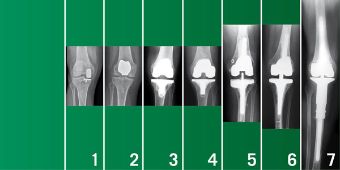

Spektrum Gelenkersatz am Knie

© Orthopädische Universitätsklinik Regensburg

Das Spektrum der endoprothetischen Versorgung

Von links nach rechts: (1) Unikondylärer Gelenkersatz (Schlitten), (2) Ersatz des Kniescheibengleitlagers, (3) und (4) bikondylärer Oberflächenersatz (Doppelschlitten) mit und ohne Erhalt des hinteren Kreuzbandes, (5) achsgeführte Prothese, (6) und (7) Tumorendoprothesen